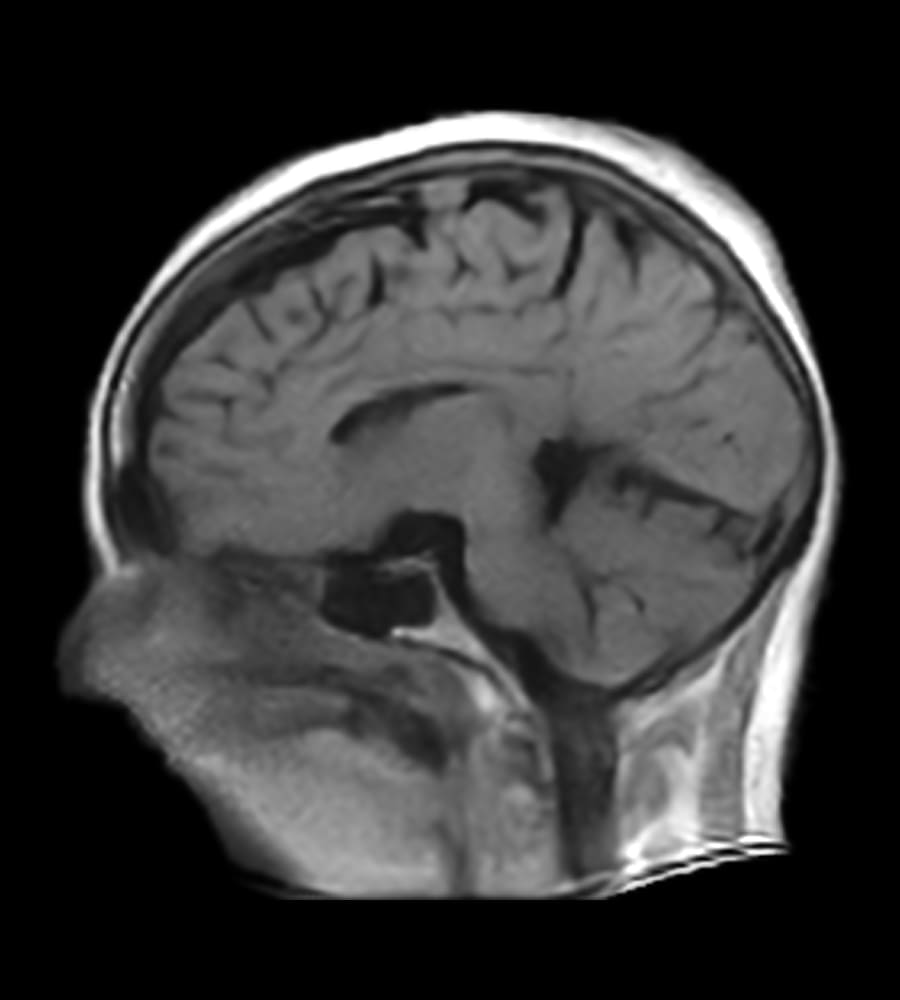

Clinical Images

Clinical case types: Headache, Migraine, Multiple Sclerosis, Micro Vascular Disease and Tumor Routine Follow-up.